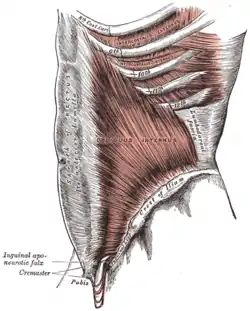

Plan of ossification of the hip bone The Obliquus internus abdominis

The Obliquus internus abdominis Muscles of the iliac and anterior femoral regions